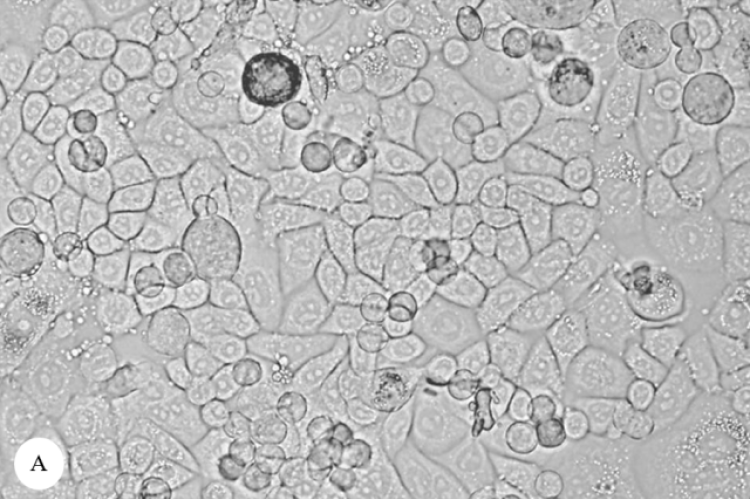

ArticleViewAbstractPharmacognosy Journal,2025,17,6s,362-365.DOI:10.5530/pj.2025.17s.107Published:December 2025Type:Original ArticleFree Radical Scavenging and Anticancer Activities of Methanolic Twig Extract of Annonaceae PlantSawitree Wongtangtintharn, Sirirath McCloskey, Rungruedee Thiwthong, U-sa Thongpairoj, and Surapong Rattana Sawitree Wongtangtintharn1, Sirirath McCloskey2, Rungruedee Thiwthong3, U-sa Thongpairoj3, Surapong Rattana4* 1Department of Animal Science, Faculty of Agriculture, Khon Kaen University, Khon Kaen, THAILAND. 2Department of Chemistry, Faculty of Science, Khon Kaen University, Khon Kaen, THAILAND. 3Department of Biology, Faculty of Science, Mahasarakham University, Maha Sarakham, THAILAND. 4Division of Science, Faculty of Education, Nakhon Phanom University, Nakhon Phanom, THAILAND. Abstract:Introduction: The Annonaceae family represents a promising source of bioactive compounds with potential therapeutic applications. This study aimed to comprehensively evaluate the antioxidant and anticancer potential of methanolic twig extracts from seven Annonaceae species. Methods: Twig specimens from Cananga latifolia, Goniothalamus elegans, Goniothalamus tamirensis, Melodorum fructicosum, Polyalthia dubia, Polyalthia cerasoides, and Uvaria fauveliana were subjected to standardized methanolic extraction. Antioxidant activity was assessed using DPPH radical scavenging assay. Anticancer potential was evaluated through Sulforhodamine B assay against three human cancer cell lines and normal human dermal fibroblasts at 25 μg/mL concentration. Results: Goniothalamus elegans demonstrated exceptional antioxidant activity (IC50 = 5.62 ± 1.21 μg/mL) comparable to ascorbic acid. In anticancer evaluation, G. elegans exhibited remarkable cytotoxicity against MCF-7 (95.19 ± 0.62%) and HeLa (94.46 ± 1.69%) cancer cells while demonstrating exceptional selectivity with minimal toxicity toward normal cells (19.72 ± 1.19%). Melodorum fructicosum showed highest activity against HT-29 colon cancer cells (75.84 ± 1.57%). Conclusions: Goniothalamus elegans demonstrated exceptional dual bioactivity with both potent antioxidant properties and selective anticancer effects. The remarkable selectivity indices and broad-spectrum anticancer activity suggest significant clinical potential. These findings provide scientific validation for traditional medicinal uses of Annonaceae species. Keywords:Annonaceae, Anticancer, antioxidant activity, Cancer cell selectivity, DPPH assay, Goniothalamus elegansView:PDF (1.06 MB) PDF Images Morphological changes in MCF-7 cells. A: Non-cytotoxic MCF-7 cells (control). B: MCF-7 cells treated with methanolic G. elegans twig extract at 25 μg/mL showing significant cell death and morphological alterations ‹ Identification of Phytochemicals and Antibacterial Activity of South Sulawesi Propolis (Apis mellifera) Using TLC and LC-MS/MSQTOF up Comprehensive Quality Evaluation: Flow Characteristics, Microscopy and Phytochemical Screening of Terminalia chebula ›